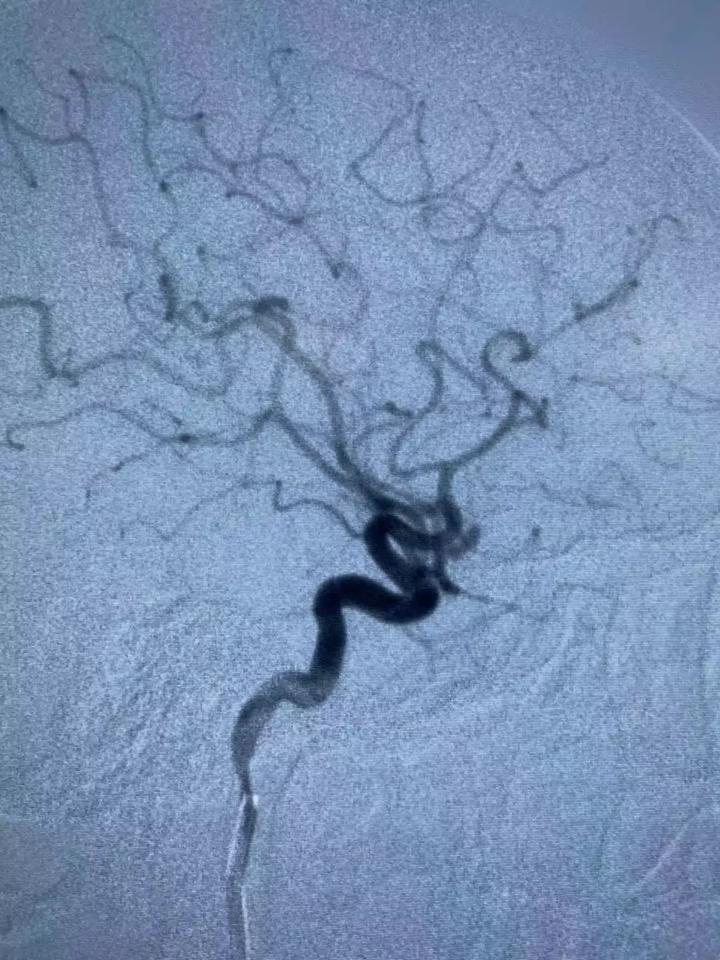

△脑血管造影检查图像

神经外二科程化坤主任表示,通过脑血管造影检查显示,患者脑出血原因是动脉瘤破裂,患者左侧大脑中动脉分叉部位长了一个动脉瘤,动脉瘤呈串珠状,长8毫米,宽3毫米。